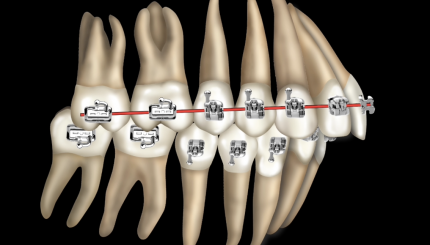

Класс 2 , низкий угол. Подход к лечению

Класс II, высокий угол. Подход к лечению.

Класс III, низкий и высокий угол. Подход к лечению

Клинический случай. Ребенок, II класс

Разбор кейса. MLD, ребенок, техника направленного роста